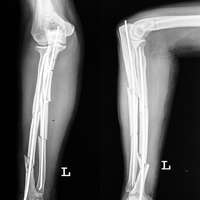

Case:1 Polytrauma Case (Multiple Fractures in Ipsilateral Limb)

Pre-Op Hip (AP & Lateral)

Pre-Op Knee (AP & Lateral)

Post-Op Hip

Post-Op Knee

4 Months Post Operative X-ray showing #s united

3 Months Follow up